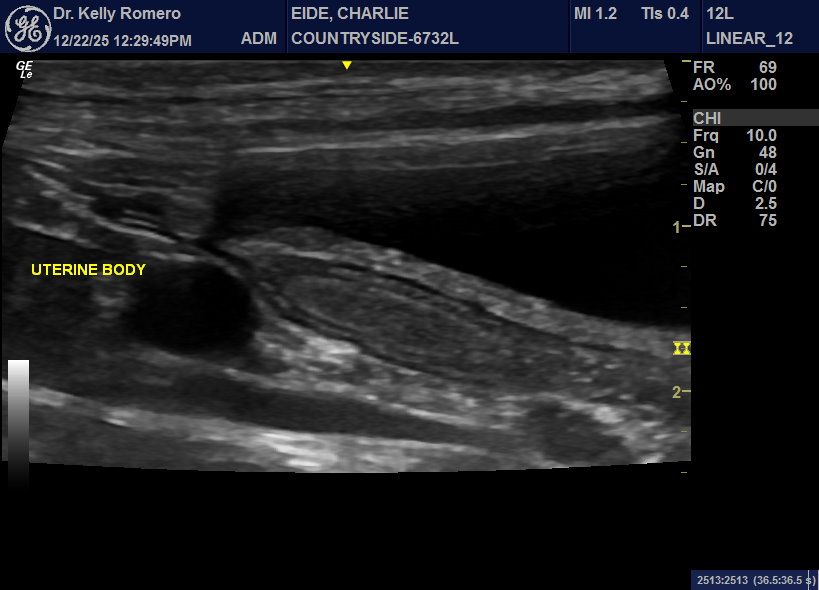

8 month old FI Golden with no clinical symptoms. pcDVM did wellness blood work one week ago- WBC was 35,000 with all cell lines elevated. Two weeks ago, owners notes some vaginal bleeding (mild). One week ago (when blood work run), vaginal discharge became more clear (still mild) and behaviorally, the male neutered dog in the house became interested and the female is receptive. Only findings I am wondering about were both ovaries appear to have active follicles (was expecting that in just one) and quite plump mes. lns. VIN search=not normal to have elevated WBC during estrus. Thoughts?

Looks like cystic ovaries and early pyometra to me and juvenile or reactive LN. OVH if not intended for breeding.

Hi Erick, thank you. – For the pyo portion, are you concerned about the luminal echogenicity in the uterine body moreso than the horns?